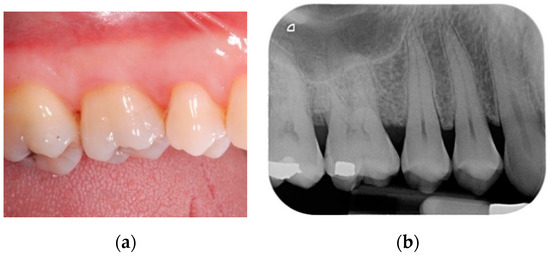

All patients were treated under local anesthesia (articaine 4% with adrenaline 1:100,000). Incisions were performed with a 15b and/or 15c scalpel blade and papillae were preserved in the areas to be regenerated following a previously described technique [25]. Incisions were extended to the adjacent teeth in case multiple sites had to be treated. A full thickness flap was elevated in order to get access to the root and the periodontal intrabony defect (Figure 1a,b); a combination of ultrasonic device and manual curettes was used to debride the area and to remove calculus and inflammatory tissue. The intrabony component of the defect was then filled by a composite graft consisting of nanohydroxyapatite powder (NHA) with crystals varying in size between 70 and 100 nm (Neo Active Apatite, Ghimas, Casalecchio di Reno, Italy) mixed with poly lactic-co-glycolic acid (PLGA) (Fisiograft Gel, Ghimas, Casalecchio di Reno, Italy) (Figure 2a). The mix ratio was 1:1 by volume. The buccal flap was then slightly released by longitudinal periosteal incision and 5.0 monofilament sutures were used to obtain primary soft tissue closure with vertical mattress sutures (Figure 2b).

Figure 1.

(a) Pre-operative periapical radiograph; (b) A full thickness flap was elevated in order to get access to the root and the periodontal intrabony defect.